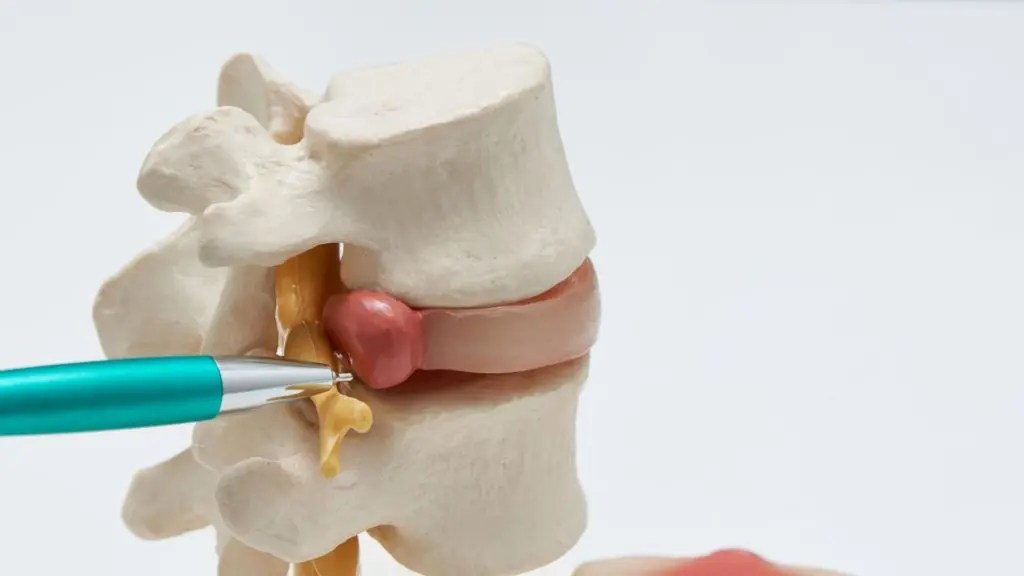

Herniated Disc In Back Recovery Time . What happens to my herniated disc if i don’t have surgery? Signs a herniated disc is healing: A herniated disk occurs when some of the softer material inside the disk pushes out through a crack in the tougher outside of the. A herniated disc tends to heal gradually and usually progresses through stages, each with its own characteristics and challenges. While every individual is different, here is a general timeline for when to expect to get back to regular activity and exercise following. The average amount of time it takes for a herniated disk to heal is four to six weeks, but it can get better within a few days depending on how severe the herniation was. A study of patients with different sized herniations showed that by six months to one year, herniated disc material. The ultimate guide to recovery. The good news is that in most cases — 90% of the time — pain caused by a herniated disc will go away on its own within six months.

The good news is that in most cases — 90% of the time — pain caused by a herniated disc will go away on its own within six months. While every individual is different, here is a general timeline for when to expect to get back to regular activity and exercise following. The average amount of time it takes for a herniated disk to heal is four to six weeks, but it can get better within a few days depending on how severe the herniation was. A study of patients with different sized herniations showed that by six months to one year, herniated disc material. A herniated disk occurs when some of the softer material inside the disk pushes out through a crack in the tougher outside of the. A herniated disc tends to heal gradually and usually progresses through stages, each with its own characteristics and challenges. What happens to my herniated disc if i don’t have surgery? Signs a herniated disc is healing: The ultimate guide to recovery.

Herniated Disc In Back Recovery Time A herniated disc tends to heal gradually and usually progresses through stages, each with its own characteristics and challenges. What happens to my herniated disc if i don’t have surgery? A herniated disk occurs when some of the softer material inside the disk pushes out through a crack in the tougher outside of the. A herniated disc tends to heal gradually and usually progresses through stages, each with its own characteristics and challenges. A study of patients with different sized herniations showed that by six months to one year, herniated disc material. The average amount of time it takes for a herniated disk to heal is four to six weeks, but it can get better within a few days depending on how severe the herniation was. The ultimate guide to recovery. Signs a herniated disc is healing: While every individual is different, here is a general timeline for when to expect to get back to regular activity and exercise following. The good news is that in most cases — 90% of the time — pain caused by a herniated disc will go away on its own within six months.